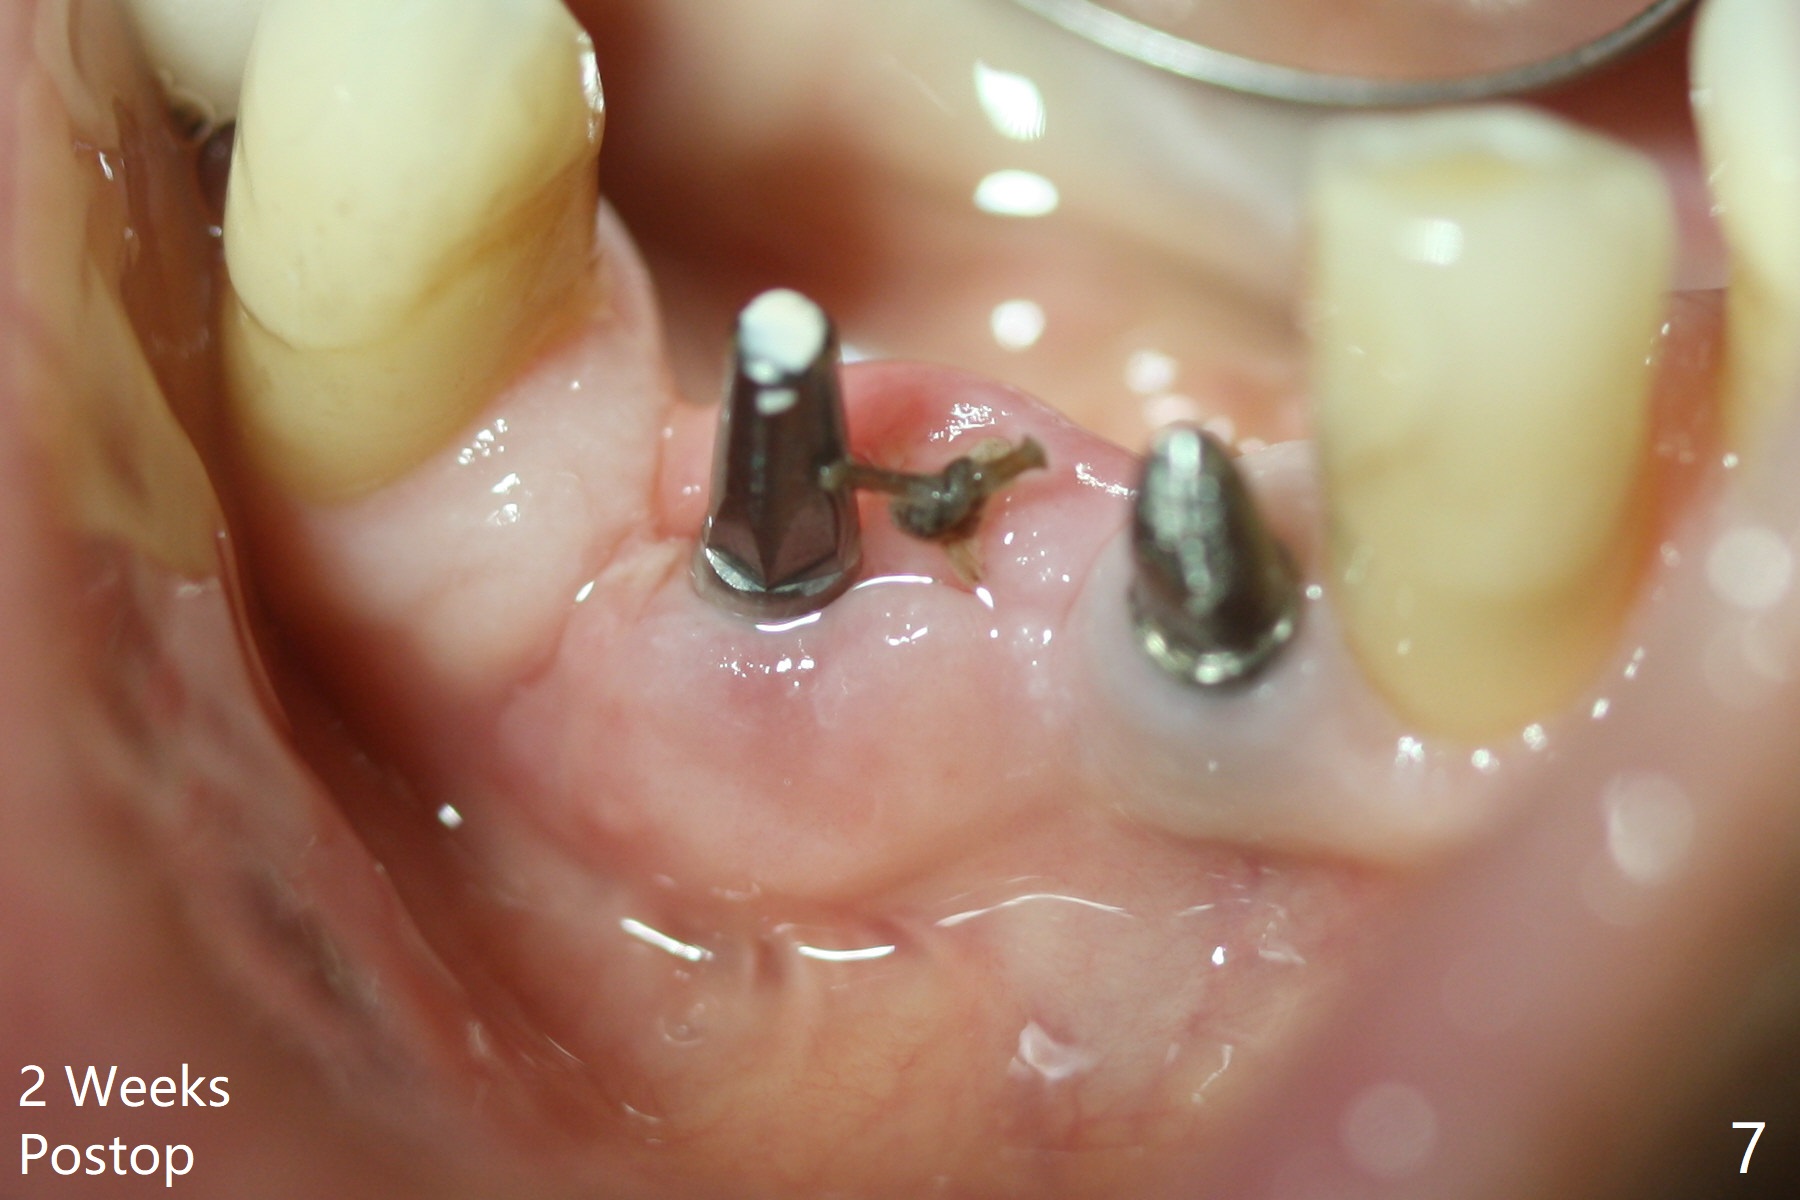

After removing #23-26 FPD and the 3x14 mm 1-piece implant at #26 (Fig.1,2 *), a new osteotomy is initiated in the narrow ridge (after ridge top reduction) approximately at #25 (Fig.2 <). Following placement a 2x10(4) mm implant at #25 (Fig.3-5) and Osteogen plug in the osteotomy at #26, Vanilla graft is placed around the implant, especially buccal. Periodontal dressing is applied after suturing. The buccal and lingual flaps are erythermatous and edematous without pain 8 days postop (Fig.6). The wound seems to be healing 2 weeks postop (Fig.7), no sign of osteonecrosis. With placement of a 2 mm implant at #25 (Fig.8 (>: bone graft buccally)), the buccal plate remains normal in thickness. When a 3 mm implant is placed at #23 (Fig.9), approximately 4 threads appear to be exposed (between arrowheads), partially due to the thick lingual plate (*).

The wound at #25 seems to heal 1 month postop; after prep (Fig.10,11), a provisional FPD is fabricated. Impression is taken for surgical guides of UL and LL implants. The patient requests early final restoration (Fig.12). The small implant placed lingually (Fig.12 *, 2 mm) is associated with the pleasing gingiva in color, as compared to the 3 mm one at #23 with the metal shaded gingiva.